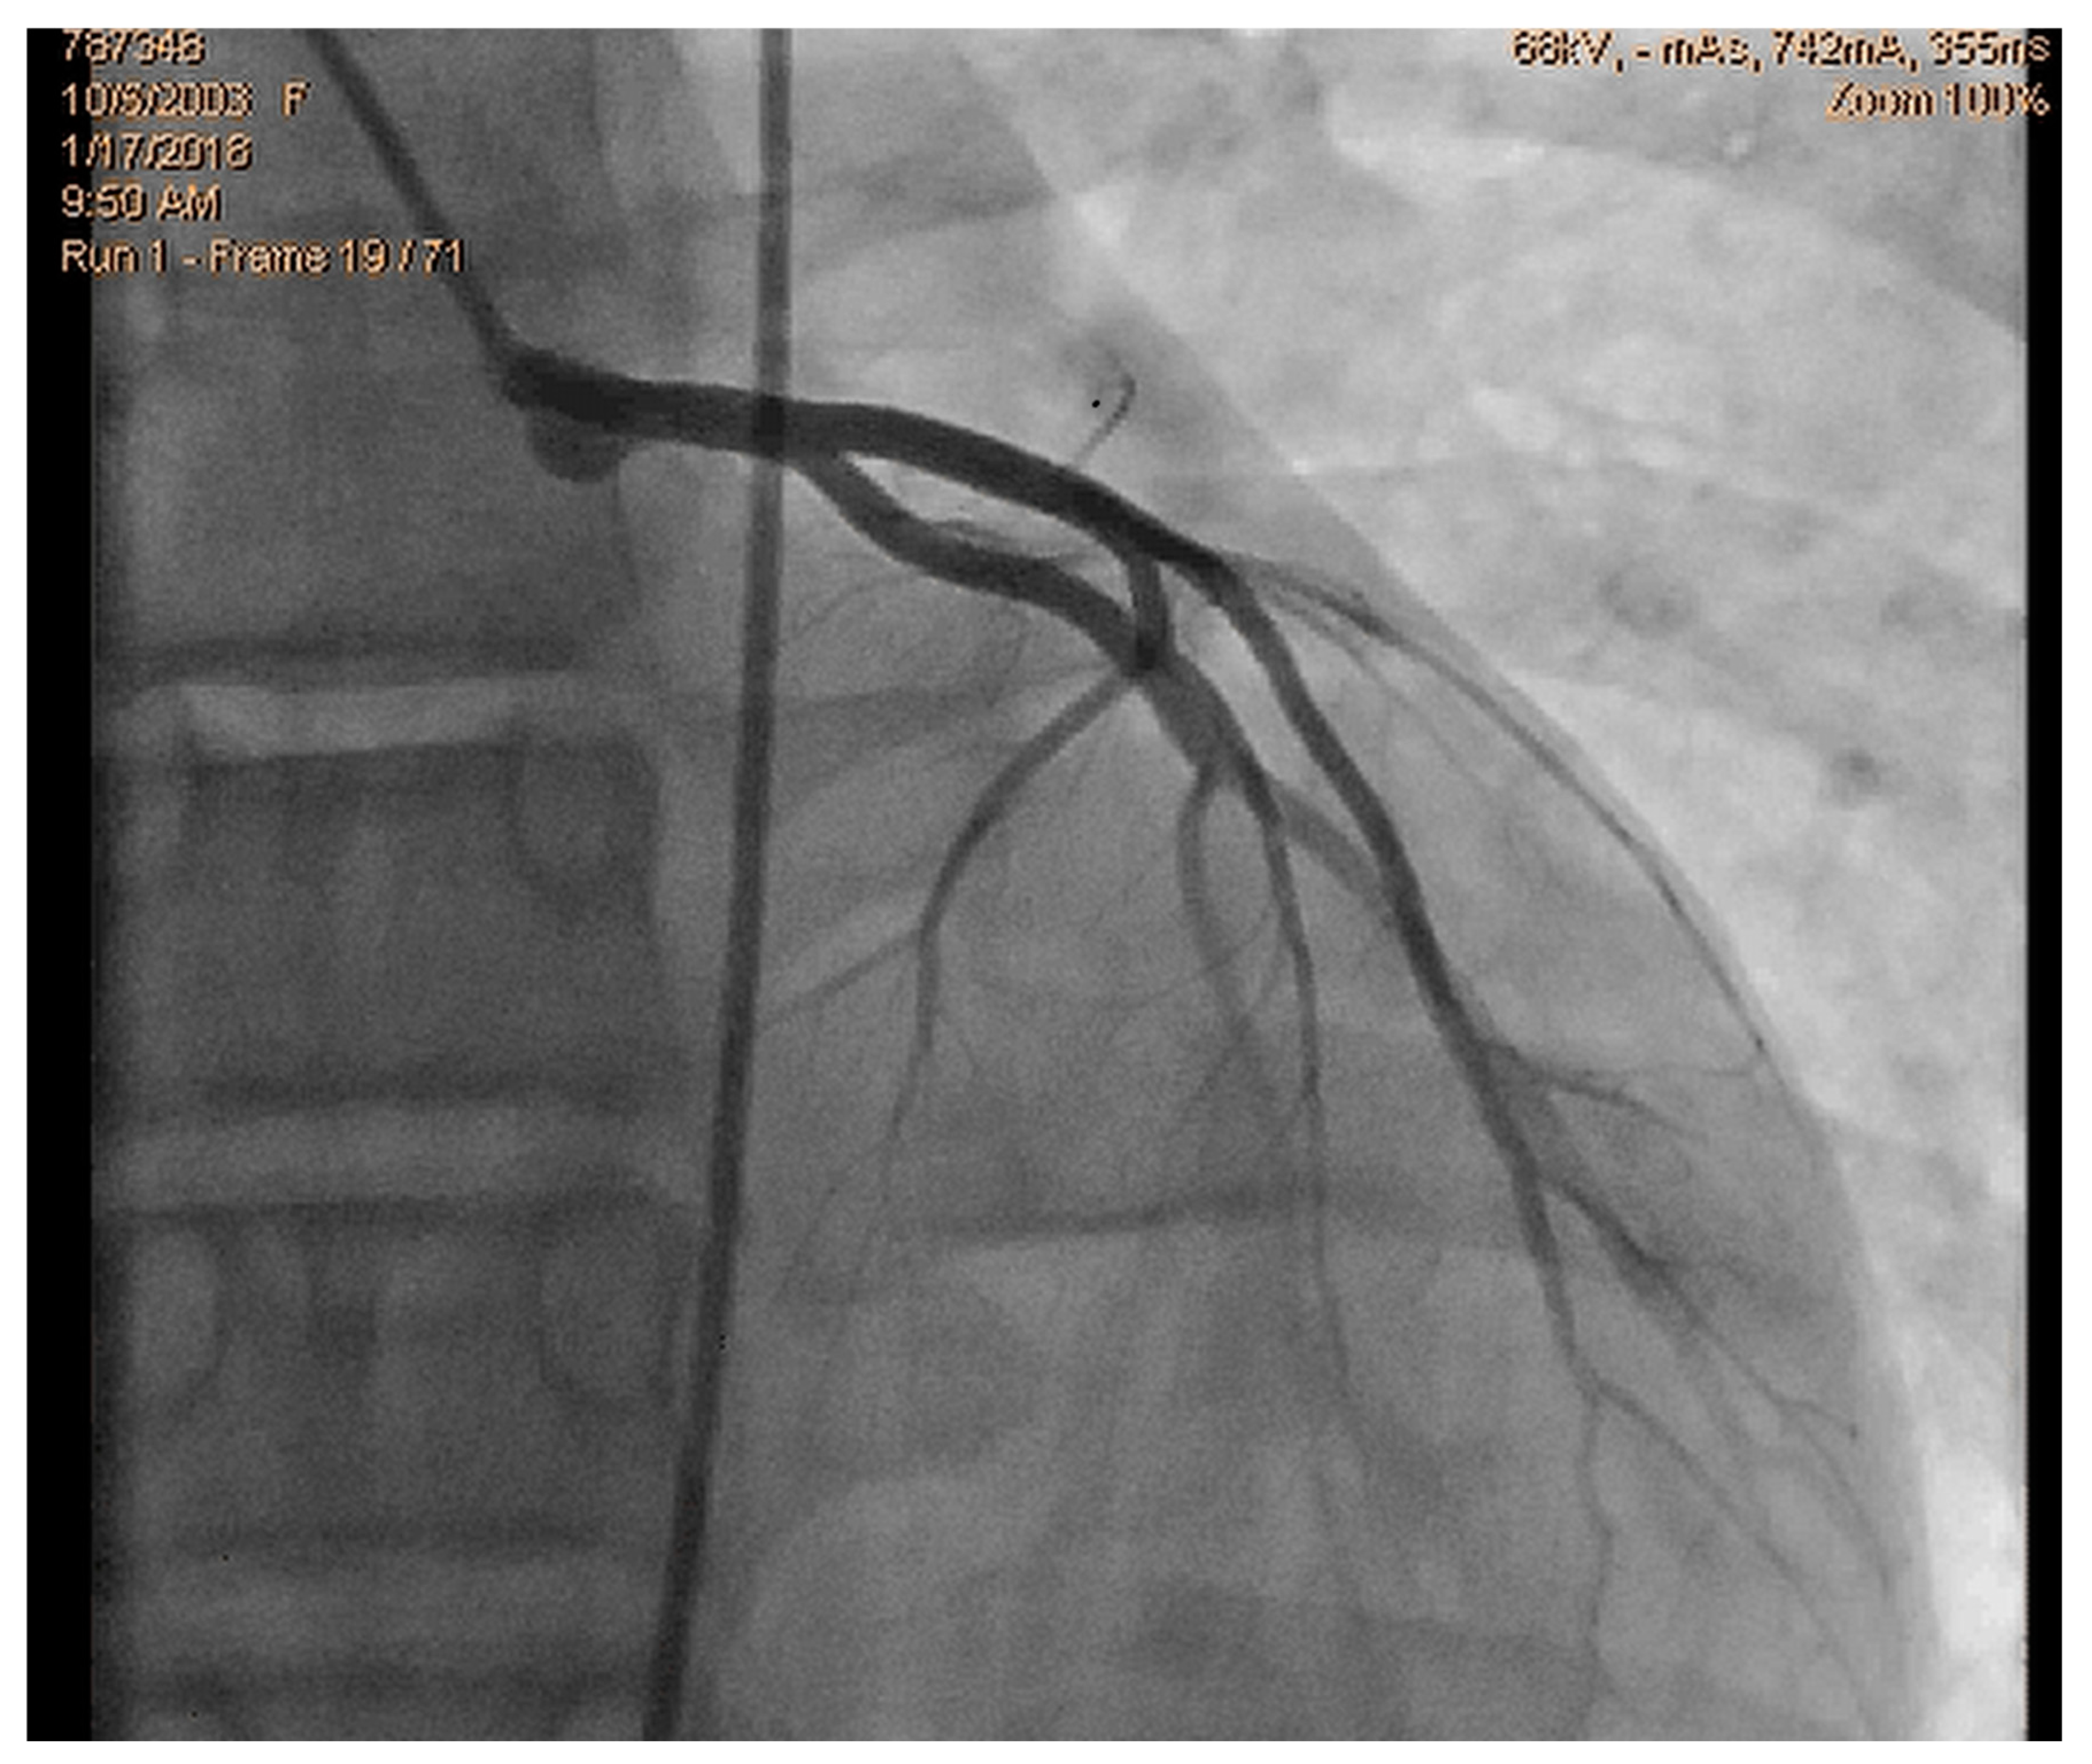

- Lopes, A.; Cotrim, C.; Martins, J.D.; Pinto, F. Exercise-induced intraventricular obstruction in a child with near syncope and chest pain during exercise. Pediatr. Cardiol. 2011, 32, 1032–1035. [Google Scholar] [CrossRef]

- Cotrim, N.; Castilho, B.; Cotrim, C.; Guardado, J.; Baquero, L. An Unexpected Finding in an Adolescent Rowing Athlete With Angina Pectoris—A Case Report. Clin. J. Sport Med. 2024, 35, 242–245. [Google Scholar] [CrossRef]

- Cotrim, C.; Almeida, A.G.; Carrageta, M. Clinical significance of intraventricular gradient during effort in an adolescent karate player. Cardiovasc. Ultrasound. 2007, 5, 39. [Google Scholar] [CrossRef]